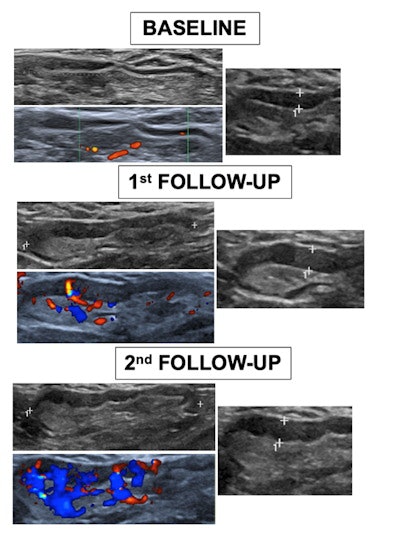

Three axillary ultrasound evaluations of the ipsilateral vaccinated arm were performed. They were done before vaccination (baseline), the week after the first dose, and the week after the second dose.

The team recorded the following characteristics: the total number of visible nodes, the maximum measurements of the diameter and cortex, Bedi's classification, and color Doppler evaluation.

Characteristics on ultrasound of patients with enlarged nodes before and after COVID-19 vaccination | |||

Baseline | 1st follow-up | 2nd follow-up | |

No. of Nodes (average) | 2.96 | 4.77 | 6.21 |

Diameter (average) | 15.8 mm | 21.1 mm | 24.0 mm |

Cortex (average) | 1.6 mm | 3.7 mm | 4.6 mm |

The researchers found that patients who were not previously infected by SARS-CoV-2 showed a more significant lymph node response compared to those who were previously infected. They also found that axillary nodes showed benign characteristics more frequently, with mild cortical thickness and preserved uniformity.